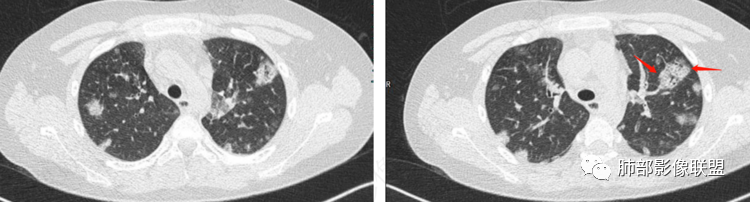

南边:

早期脓毒栓子可以,楔形。

内部低密度影都符合

这些是典型的 |

这种网格,没弄太清楚 |

是否有二元的可能?看有无其他片,对比一下。

2.影像上肺多发混合密度片影,随机分布,胸膜下分布优势,病灶边界大多隐约可辨,偏柔和,动脉血管影穿行,未见钙化、液化空洞、或明确气囊影,未见树芽征。

3.影像方面:双肺多发病灶,随机分布,且有相当部分沿胸膜下,是可以符合血流感染的。

2.表现多样,多种影像表现可同时出现,如斑片状影、小点状影、结节影、肺气囊等可在CT片上同时见到;

3.病灶比较广泛,多个肺野出现同时受累;

4.容易在短期内出现散在的肺气囊或多发的脓肿病灶;

5.病灶易变,短期内复查CT可见病灶的形态、部位、大小发生变化。

1.外围分布,胸膜下为主,两肺弥漫结节或胸膜下楔形影,边界清,周围伴有GGO

2.反晕征:往往紧贴胸膜,并且胸膜侧无环,周围GGO

3.空洞:分为两类。

第一类,偏心空洞,一侧壁厚,周围实变明显。

第二类,薄壁空洞(偏中后期):壁薄且均匀,内外壁光滑,张力高,内有气液平面、间隔影,各空洞相对独立互不相通

4.囊:张力高,壁薄,内外壁光滑,可有间隔

5.边缘收缩明显,结节密实,边缘收缩、凹陷,周围长索条影,提示吸收好转

6.胸腔积液、脓胸